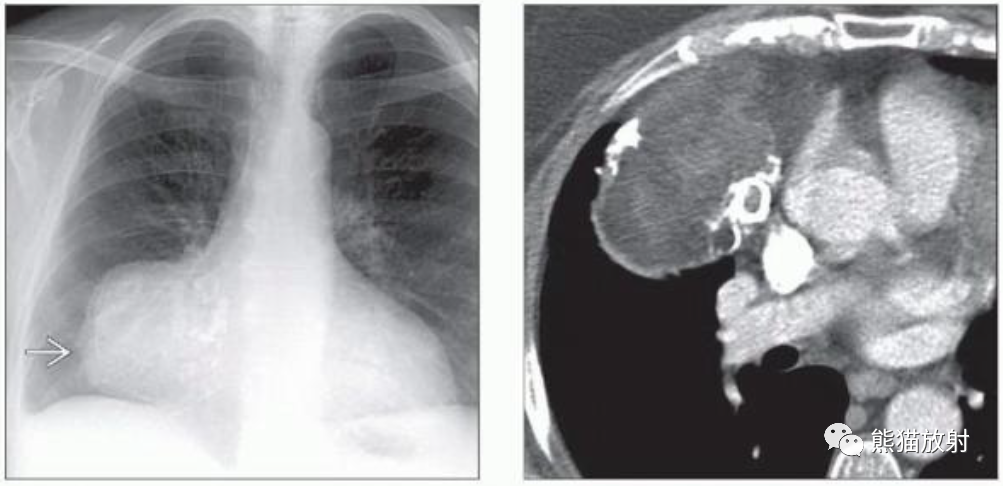

(左)17岁胸腺脂肪瘤患者,PA胸片显示左前纵隔肿块,显示肺门重叠征。胸腺脂肪瘤多见于年轻患者,无症状。

(右)胸腺脂肪瘤患者的轴位CECT显示左前纵隔肿块,位于胸腺解剖位置,脂肪密度为主,内见条状、结节状软组织密度。